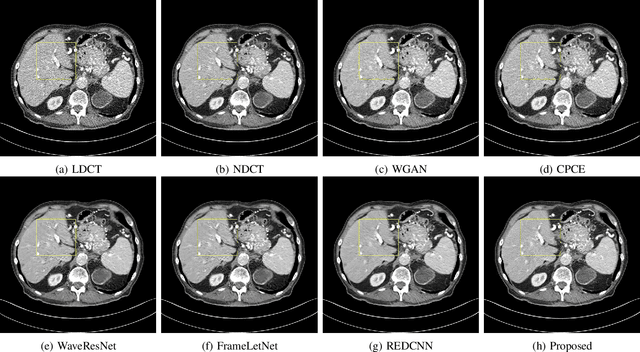

Abstract:The explosive rise of the use of Computer tomography (CT) imaging in medical practice has heightened public concern over the patient's associated radiation dose. However, reducing the radiation dose leads to increased noise and artifacts, which adversely degrades the scan's interpretability. Consequently, an advanced image reconstruction algorithm to improve the diagnostic performance of low dose ct arose as the primary concern among the researchers, which is challenging due to the ill-posedness of the problem. In recent times, the deep learning-based technique has emerged as a dominant method for low dose CT(LDCT) denoising. However, some common bottleneck still exists, which hinders deep learning-based techniques from furnishing the best performance. In this study, we attempted to mitigate these problems with three novel accretions. First, we propose a novel convolutional module as the first attempt to utilize neighborhood similarity of CT images for denoising tasks. Our proposed module assisted in boosting the denoising by a significant margin. Next, we moved towards the problem of non-stationarity of CT noise and introduced a new noise aware mean square error loss for LDCT denoising. Moreover, the loss mentioned above also assisted to alleviate the laborious effort required while training CT denoising network using image patches. Lastly, we propose a novel discriminator function for CT denoising tasks. The conventional vanilla discriminator tends to overlook the fine structural details and focus on the global agreement. Our proposed discriminator leverage self-attention and pixel-wise GANs for restoring the diagnostic quality of LDCT images. Our method validated on a publicly available dataset of the 2016 NIH-AAPM-Mayo Clinic Low Dose CT Grand Challenge performed remarkably better than the existing state of the art method.